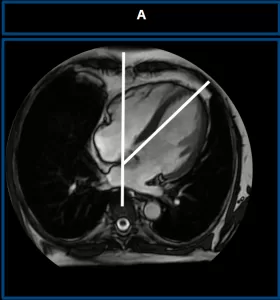

Congenital Absence of the Left Pericardium

Axial chest MRI of a healthy control (A) demonstrates normal cardiac rotation. A vertical reference line is drawn along the spine. The cardiac axis forms an angle of less than 60° indicating normal positioning.

Axial T1-weighted MRI (B) shows excessive clockwise rotation of the heart, with a cardiac axis angle greater than 60°, a characteristic finding of left pericardial agenesis. Axial T2-weighted MRI (C) confirms the abnormal cardiac orientation, supporting the diagnosis.